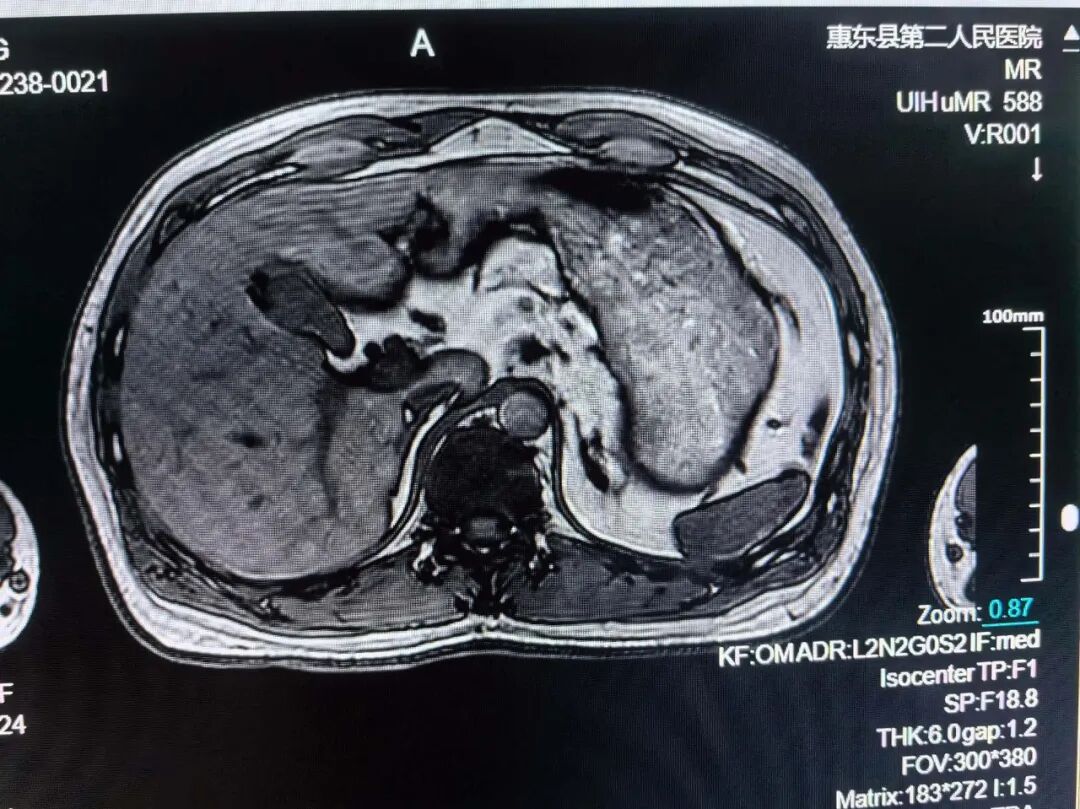

肝胆脾胰MRI检查

肝脏、胆系、胰腺、脾脏的原发性或转移性肿瘤,以及肝海绵状血管瘤;肝寄生虫病:如肝包虫病;弥漫性肝病:如肝硬变、脂肪肝、色素沉着症;肝、胆、胰、脾先天性发育异常;胆道梗阻:明确梗阻的部位与性质;肝脓肿;⑦肝局限性结节增生和肝炎性假瘤;⑧手术、放疗、化疗及其它治疗效果的随访和观察;⑨胰腺炎及其并发症。